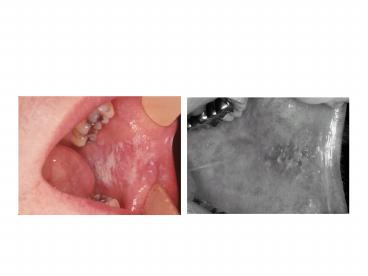

Cheek chewing

• Morsicatio buccarum, chronic chewing of cheek,

• DDx idiopathic leukoplakia, lichen planus, linea

alba, chemical (aspirin) or thermal burn,

toothpaste reaction, cheek chewing

• Description-large ulcerated hyperkeratotic

macule, ragged, appears to be pealing off, white

and red, may or may not wipe off